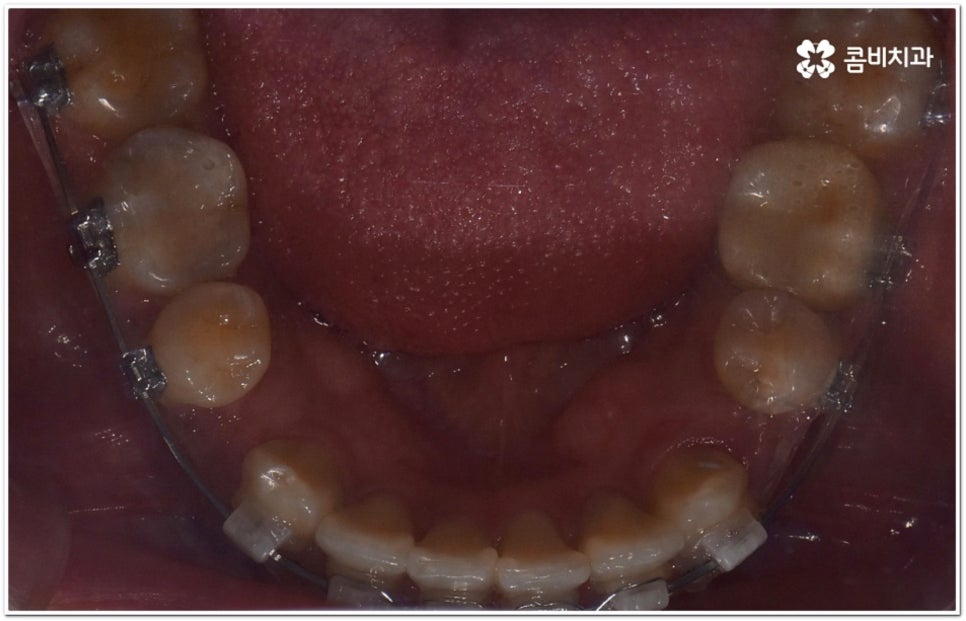

또한 구조적인 부분에 원인이 있었다면 교정 치료를 받은 후에도 원래대로 치열이 돌아가려고 하는 회귀 경향이 좀 더 강하게 일어날 수 있어요. 그렇기 때문에 치과에서 말씀드린 유지 장치를 잘 착용하면서 사후 관리를 철저하게 해 줘야 보다 오랜 시간 동안 바른 치열을 유지하면서 이를 건강하게 사용할 수 있습니다.

가철식(뺐다 꼈다 할 수 있는) 유지 장치는 눈에 잘 띄지 않고 식사를 할 때나 중요한 자리에서 잠깐씩 뺄 수 있다는 장점을 가지고 있지만 착용하는 시간이 부족하게 되면 혹여 치열이 다시 삐뚤어지거나 교합이 어긋나게 되어 심한 경우 재교정을 받아야 하는 상황까지도 이를 수 있기 때문에 교정이 끝난 초기에는 환자분들께서 주의를 기울여서 불가피한 경우가 아니라면 계속해서 착용을 해주시길 권고드리고 있어요. 그 이후에는 치료하신 치과의 안내에 따라 착용 시간을 줄여가면서 정기적인 검진을 받으시면서 관리를 해주시는 게 좋아요. 이에 반해 고정식 유지 장치는 착용 시간을 신경쓰지 않아도 되지만 부착시킨 철사로 인해 칫솔질이 어려워지고 치석이 잘 생기는 등 위생 문제가 발생할 수 있다는 점을 유의해야 하므로 주기적으로 검진을 받으면서 스케일링 치료를 통해 구강 내 위생 관리를 철저하게 해 주면 도움이 될 거예요. 가장 좋은 것은 고정식 유지장치와 가철식 유지장치를 둘 다 착용을 하시는 게 도움이 되므로, 치료를 담당하시는 원장님과 자세히 상담받아보시길 권장 드려요.